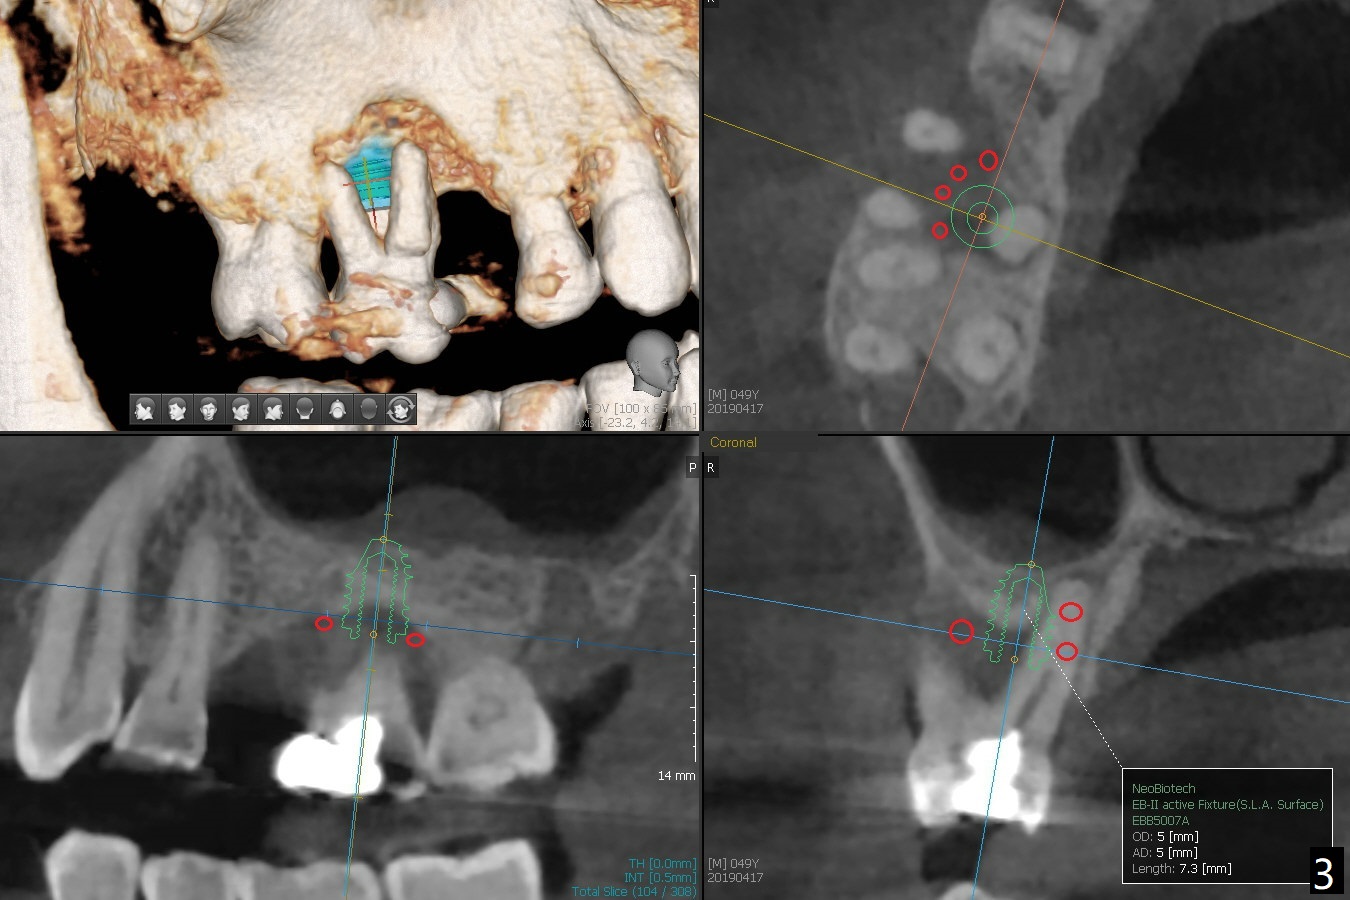

A 49-year-old man (patient of ours for 7 years) has severe bone loss and buccal recession at #3 with missing tooth at #4 (Fig.1,2,5). Short implants will be placed as palatal as possible (Fig.3,4 green) with buccal bone graft (red circles). PRF will be prepared for membranes and sticky bone.